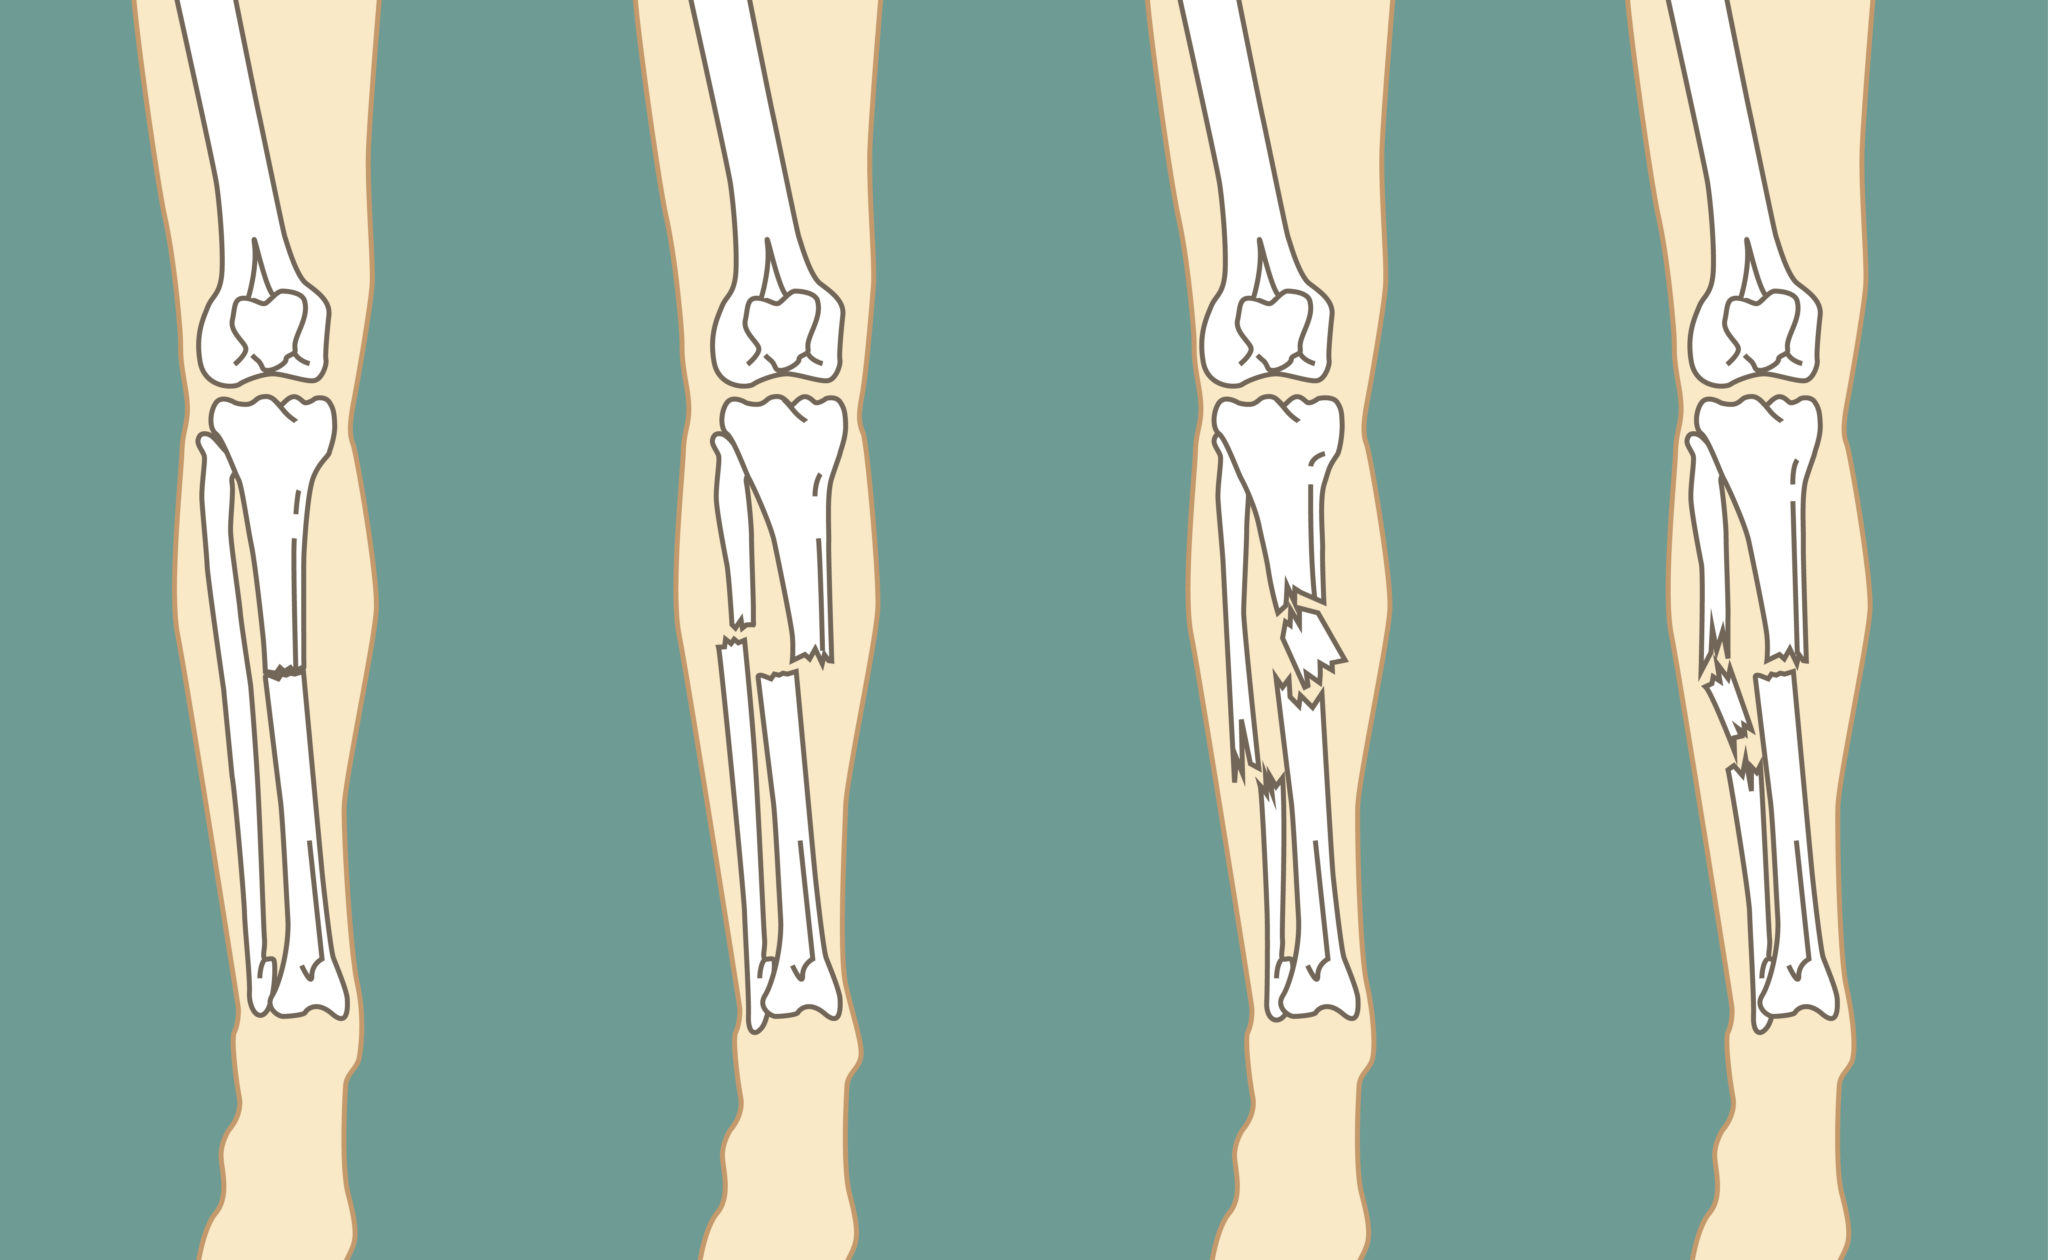

Довольно часто ситуация отягощается присутствие смещения отломков. А также данное повреждение может сопровождаться переломом таза, рёбер, других костей конечности, получением травм живота и прочим. Получить такое повреждение можно по самым различным причинам. Так, она может быть получена в ходе дорожно-транспортного происшествия, неудачного падения, в случае катастрофы или производственной травмы. Вне зависимости от первопричин появления и особенностей конкретной ситуации необходимо незамедлительно обращаться за профессиональной помощью к квалифицированным специалистам. Только проведение профессиональных реабилитационных мероприятий поможет больному достичь скорейшего выздоровления, вернуть утраченную двигательную активность и избежать многочисленных осложнений. Для этой цели вы всегда можете воспользоваться услугами профессиональных специалистов частного центра реабилитации «Исток» в Беслане.

Основные симптомы перелома берцовой кости

Точный перечень симптомов и их интенсивность при наличии такого повреждения в каждом отдельном случае будет персональным. Тем не менее у больного всегда присутствует сильная и резкая боль. А также его голень деформируется, она может быть укорочена, скручена или углообразно искривлена. Ещё в месте повреждения появляется отёчность, увеличение в объёме, многочисленные кровоподтёки, появляется крепитация и ненормальная подвижность ноги. При этом больно не имеет возможности двигать ногой и опираться на неё. Если же перелом открытый, то присутствует рана, в которой заметны отломки костей.

При появлении такой тревожной симптоматики необходимо незамедлительно обращаться за помощью к опытным специалистам. Доктор проведёт осмотр и обследование больного с обязательным применением рентгена. Такое исследование поможет определить характер смещения, количество отломков, присутствие иных повреждений. Для получения более конкретной информации может быть назначено проведение КТ. Последующее лечение в соответствии с особенностями может быть оперативным с фиксацией отломков кости с применением шрифтов, пластин и прочих аппаратов внешней фиксации. Или же может быть применимо консервативное лечение с наложением гипса. А после такой меры необходимо воспользоваться обязательной реабилитационной программой, без которой нельзя достичь полноценного выздоровления. И в этом случае вам помогут профессиональные специалисты современного реабилитационного центра «Исток».